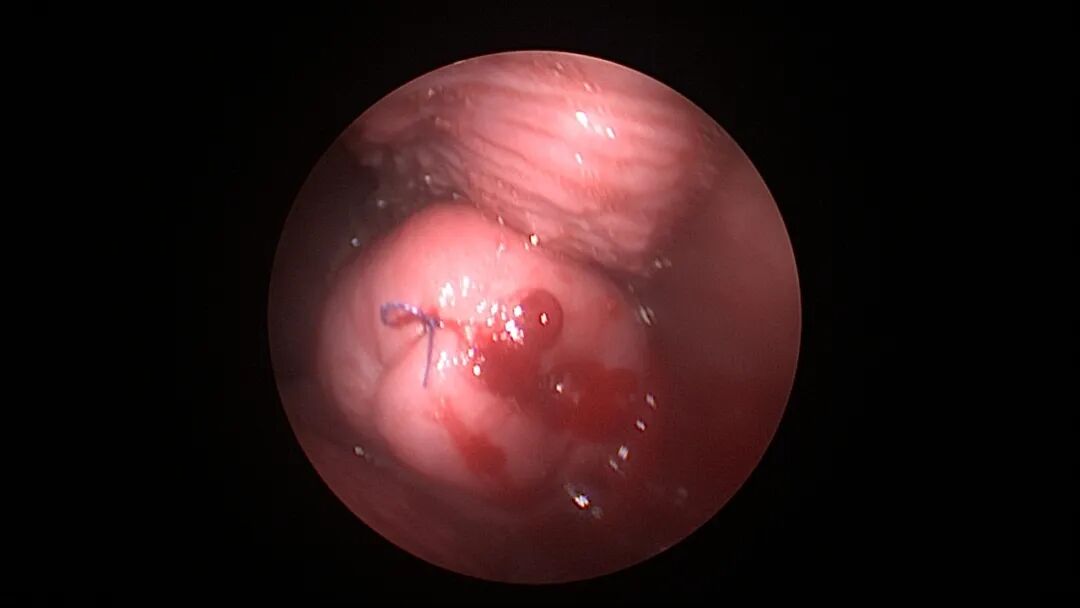

取胚术后丝线挂钩固定节育环图片及视频

子宫腺肌症内膜息肉切除后丝线挂钩固定曼月乐并电凝图片及视频

异常子宫出血内膜增生节育环尾丝挂钩固定曼月乐图片及视频